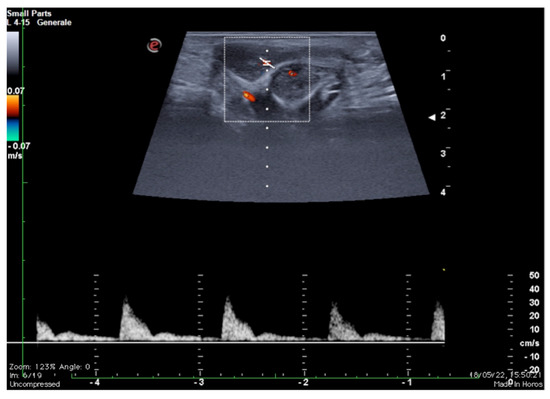

The study of the venous leak and its characterization in young patients with ED represents a diagnostic challenge. The microsurgical approach and vascular embolization techniques are assisted by an adequate anatomical study and precise evaluation of the escape sites [12,13,14,15]. As it is known, two distinct venous drainage systems are identifiable: a deep one, which drains the cavernous bodies and the glans through the deep dorsal vein directly into the retro-pubic plexus, and a superficial system, which drains the skin and adjacent tissues through the external pudendum veins directly into the large saphenous veins [12,13,14,15]. Imaging, therefore, remains the most appropriate recourse both for the selection of patients with possible erective deficit due to vascular etiology through the colour-Doppler and Doppler-pulsed study of the cavernous arteries after pharmacological stimulation (Figure 2) and to obtain anatomical details of the superficial and deep venous system of the penis [16,17,18].

Figure 2.

Functional impotence (erection duration) in a 39-year-old patient. An EHS 3 erection is observed 10 min after the injection of 10 mg of PGE1, characterized by a reduction in diastolic component but no reversal of tracing. Findings were suggestive of insufficient erection due to a venous leak. PGE1—prostaglandins; EHS—erection hardness score.

B-mode ultrasound and pulsed Doppler performed before and after drug-induced erection are the most widely used methods before resorting to invasive instrumental investigations. As is well known, the speed and morphology of the flow-metric curve detected at pulsed Doppler varies at different times during the erective process, in close dependence to the endocavernosal pressure, therefore observing physiologically high resistance flow spectra with inversion of the diastolic component during complete erection (Figure 10).

Figure 10.

Color and pulse Doppler penile Ultrasound performed in different phases of erection. During the flaccid state (a), the waveform shows a monophasic pattern with minimal diastolic flow; during the tumescence (b), the waveform shows a progressive decrease in diastolic flow; during the full erection (c), the waveform shows a diastolic flow reversal.

Otherwise, in the presence of increased venous outflow, a persistently high diastolic velocity is observed even at maximum erection obtained by drug induction: when the diastolic velocity is greater than 10 cm/s, venous etiology of ED should be suspected. An imaging contrastographic study for evaluation of the venous circulation must be carried out to confirm the diagnosis of ED by venous outflow (Figure 2) [18,25,26].